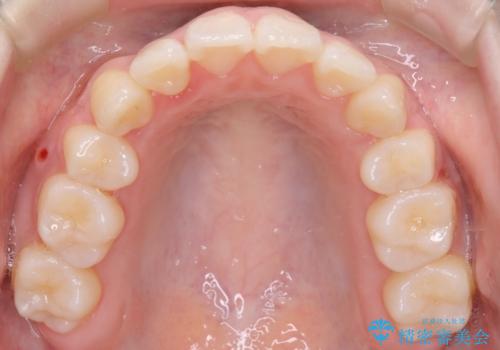

- 4番の歯を4本抜歯をし、上顎にマイクロインプラントを2本埋入し、遠心移動を行いました。

主訴のオープンバイトは改善し、抜歯をしたことで前歯が下がり綺麗になりました。抜歯矯正でしたが1年2か月という短い期間で終了しました。